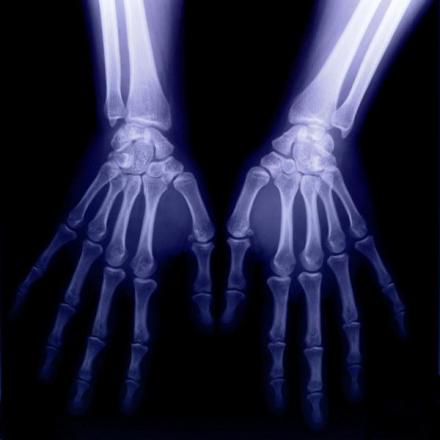

他偶然发现X射线可以穿透肌肉照出手骨轮廓,于是有一次他夫人到实验室来看他时,他请她把手放在用黑纸包严的照相底片上,然后用X射线对准照射15分钟,显影后,底片上清晰地呈现出他夫人的手骨像,手指上的结婚戒指也很清楚

这是一张具有历史意义的照片,它表明了人类可借助X射线,隔着皮肉去透视骨骼